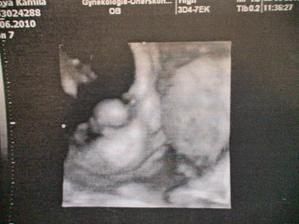

velký utz 2.6.(30tt+4) dopadl výborně, váhový odhad 1823g🙂 malá je hlavou dolů, obličejem na pravou stranu, dle hlavičky odpovídáme tt těhotenství, dle váhy jsme o týden větší🙂) placenta na zadní stěně. Doktor kontroloval srdíčko, ledviny, žaludek, páteř..měřil stehenní kost. ukazoval nám obličej na 2D utz-byly nádhreně vidět rtíky a nosík🙂 takže žádné rozštěpy nebo jiná nemilá překvápka🙂 a dostali sme i 3D fotečku. Sice jen půlku obličeje, pže plod vody už je ve 31tt méně, ale stejně je nááádherná🙂 Jo a pohlaví nám ukazoval, je tam děvčátko nad vší pochybnost🙂